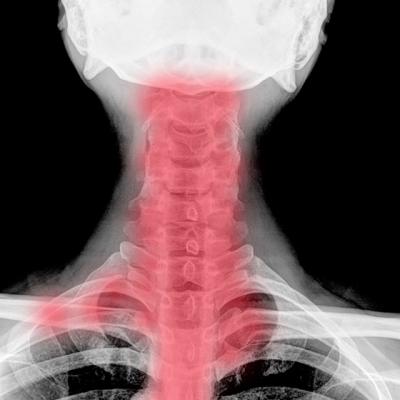

Spondiloza cervicala: cauza ametelilor si a furnicaturilor in brate

Spondiloza cervicala sau osteoartrita cervicala este o afectiune foarte des intalnita, incidenta acesteia fiind crescuta la persoanele in varsta si... Iulia Maftei (Dibu)

Spondiloza cervicala, cauza durerilor de gat

Odata cu inaintarea in varsta, oasele si ligamentele de la nivelul coloanei resimt cel mai bine trecerea anilor si se deterioreaza gradual, in... Kudika